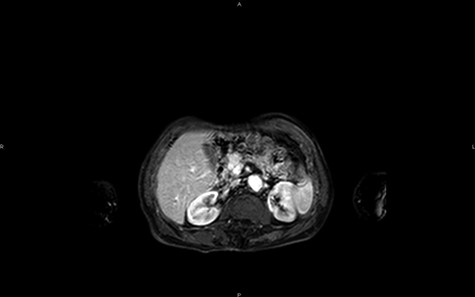

Magnetic resonance imaging (MRI) confirms the hypervascularized and atypical character of this pancreatic tumor (Figs 2 and 3). Moreover, one hepatic lesion with the same characteristics is highlighted.

MRI in coronal section, T2 phase: visualization of a compression of the main pancreatic duct.